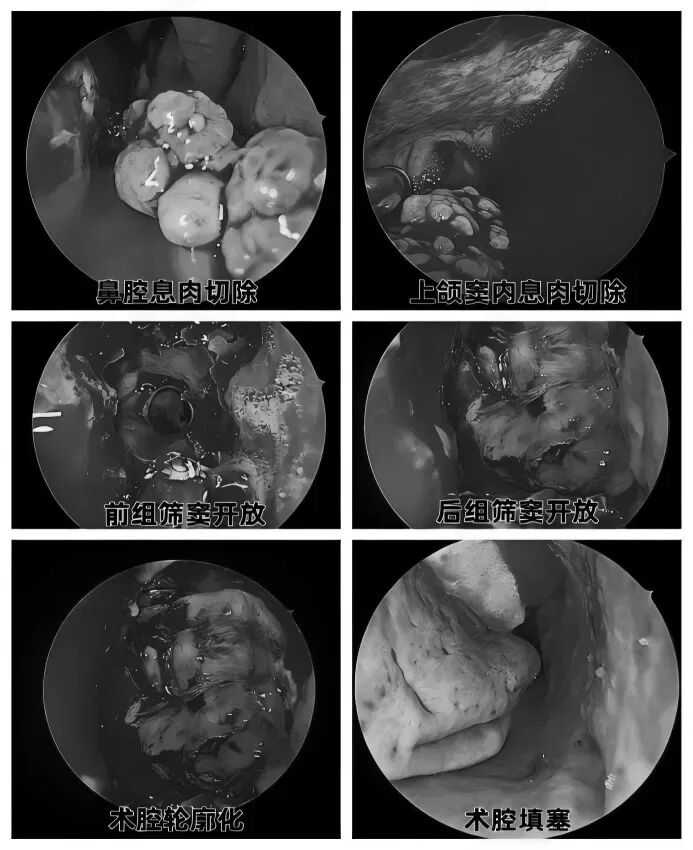

耳朵反复流脓、听力下降还有异味?当心,这可能是慢性化脓性中耳炎的症状。由于早期症状时好时坏,很多人觉得不是大问题,但拖延不治可能对听力造成不可逆的损伤。今天我们就来认清它的真面目,学会如何科学应对。 什么是“慢性化脓性中耳炎”? 慢性化脓性中耳炎,俗称“灌耳心”,典型症状包括耳内反复流脓(常为脓性分泌物,严重时可伴有臭味)、听力下降以及耳鸣等,部分患者还可能伴有眩晕。很多人是从小时候就开始出现症状,尤其是耳朵进水后容易急性发作或加重,成年后,听力持续减退往往成为主要困扰。 如果不及时治疗,炎症可能“向上”蔓延到颅内,引发脑膜炎、脑脓肿等危及生命的严重并发症。也可能侵犯面部神经或平衡器官,导致面瘫、持续眩晕或平衡障碍。最直接的后果是听力会不可逆地下降,严重时可能导致完全失聪。 “慢性化脓性中耳炎” 如何治疗? 慢性化脓性中耳炎的基础治疗需先用双氧水或生理盐水清洗耳道脓液,再滴入敏感抗生素耳液(如氧氟沙星滴耳液)。急性发作或重症时需口服或静脉注射抗生素并辅以抗炎药。若药物控制不佳或已有器质性病变,则需手术,包括乳突切除术清除病变组、鼓膜成形术修复穿孔鼓膜、听骨链重建术改善传音功能及胆脂瘤清除术清除胆脂等。 患者常见问题解答 问 手术后多久能恢复听力? 答 术后恢复情况与手术方式、个人身体情况有关。若为鼓膜修补手术,术后1—3个月左右,听力会逐渐改善,若进行听骨链重建手术,通常需要 3 到 6 个月,听力才能趋于稳定。术后需定期复查,监测听力恢复情况。 问 儿童患者能手术吗? 答 如果孩子的病情确实需要手术,家长不用太担心,儿童也是可以接受手术治疗的。医生会根据孩子的年龄大小、病情严重程度,选择最适合的手术方式,比如现在常用的微创技术,就能尽量减少手术对孩子耳朵的创伤,让孩子恢复的更好。 问 如何预防复发? 答 术后严格遵医嘱用药、复查,避免感冒及耳部进水,保持鼻腔通畅,减少咽鼓管阻塞。 贵州航天医院耳鼻咽喉科简介 张光进 中共党员,耳鼻咽喉科主任,副主任医师 临床擅长:对耳鼻喉头颈常见病的诊治具有丰富的临床经验,擅长鼻内镜、耳内镜、耳显微、头颈咽喉部肿瘤及眩晕手法复位等的诊疗。 曾先后前往第三军医大学西南医院、复旦大学耳鼻喉科医院、上海新华医院及北京友谊医院进修学习;遵义市医学会常务委员;主持及参与级科研课题2项,发表专业论文10余篇。 陈维信 九三学社社员,耳鼻咽喉科主任医师 临床擅长:对耳鼻咽喉科常见疾病的诊治具有丰富的临床经验,擅长耳、鼻、喉及头颈部位的手术。 曾先后前往上海交通大学附属仁济医院耳鼻喉-头颈外科、北京大学人民医院耳鼻喉-头颈外科参加鼻内镜外科进修学习。中国睡眠研究会委员,贵州省医学会耳鼻喉-头颈外科学分会委员,贵州省耳鼻喉-头颈外科学会理事,贵州省医学会变态反应学分会委员,贵州省防聋治聋技术指导组专家,遵义市耳鼻喉科分会副主任委员,遵义市医疗事故鉴定专家库成员;主持省部级科研课题2项,发表专业论文20余篇。 秦 晋 耳鼻咽喉科副主任医师 临床擅长:对耳鼻咽喉科常见疾病的诊治具有丰富的临床经验,擅长耳、鼻、喉及头颈部位的手术。 遵义市医学会常务委员;曾先后在第三军医大学西南医院、湖南湘雅鼻颅底培训班进修学习。 贵州航天医院耳鼻咽喉科简介 基本情况 贵州航天医院耳鼻咽喉科拥有一支经验丰富、技术精湛的医疗团队,共有医师9名,其中副高级以上专家5名,医学硕士2名,开放床位20张,拥有德国WOLF鼻窦内窥镜系统、日本奥林巴斯电子喉镜、奥林巴斯电子鼻咽镜、丹麦临床听力监测设备、声导抗仪、听觉诱发电位、耳声发射仪、美国杰西低温等离子治疗仪、杭州好克鼻窦内窥镜系统、鼻动力系统、耳显微镜、耳用电钻、微波治疗仪等设备。 专科特色 (一)耳部疾病 耳内镜下胆脂瘤切除术、III型鼓室成形术+人工听骨链重建术。 (二)鼻部疾病 内镜下鼻息肉切除术、鼻窦功能开放术。 (三)咽喉疾病 内镜下扁桃体、腺样体低温等离子切除术 (四)交叉学科 1.经鼻内镜下眶内肿瘤切除术 2.经鼻内镜下鼻腔泪囊吻合术 诊疗范围 (一)常见耳疾的诊断和治疗:中耳炎、耳聋、耳鸣等。通过各种耳科检查手段,如耳镜检查、听力测试和耳脑干听觉诱发电位检查等,准确诊断患者病情,制定个性化治疗方案。 (二)鼻炎、鼻窦炎、鼻出血等鼻科疾病的诊断和治疗:采用微创技术,如鼻内窥镜检查、低温等离子手术等,为患者提供有效的治疗方案。 (三)喉炎、声带息肉、声带白斑等喉科疾病的诊断和治疗:通过声带电子镜、喉镜等设备,准确判断患者的喉部病变,为患者提供精准的治疗方案。 (四)鼻眼、鼻颅底相关手术。